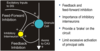

Diagram of Chemical Neurotransmission